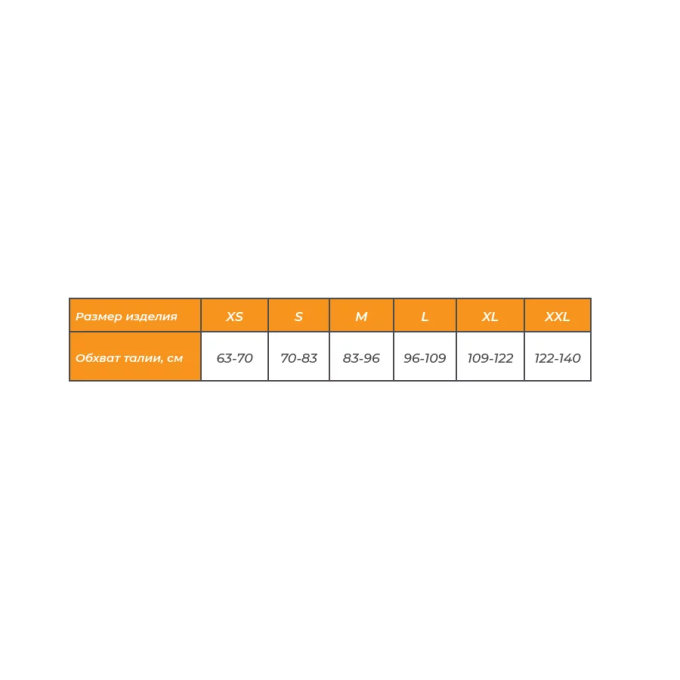

Арт: ПР-315 ус

Корсет ортопедический противорадикулитный жесткий усиленный с 4 ребрами жесткости шириной 35 см, артикул Орт.ПР-315

Арт: ПО-211

Бандаж послеоперационный с мягкой панелью шириной 20 см, артикул Орт.ПО-211 (1 панель)

Арт: ПО-212